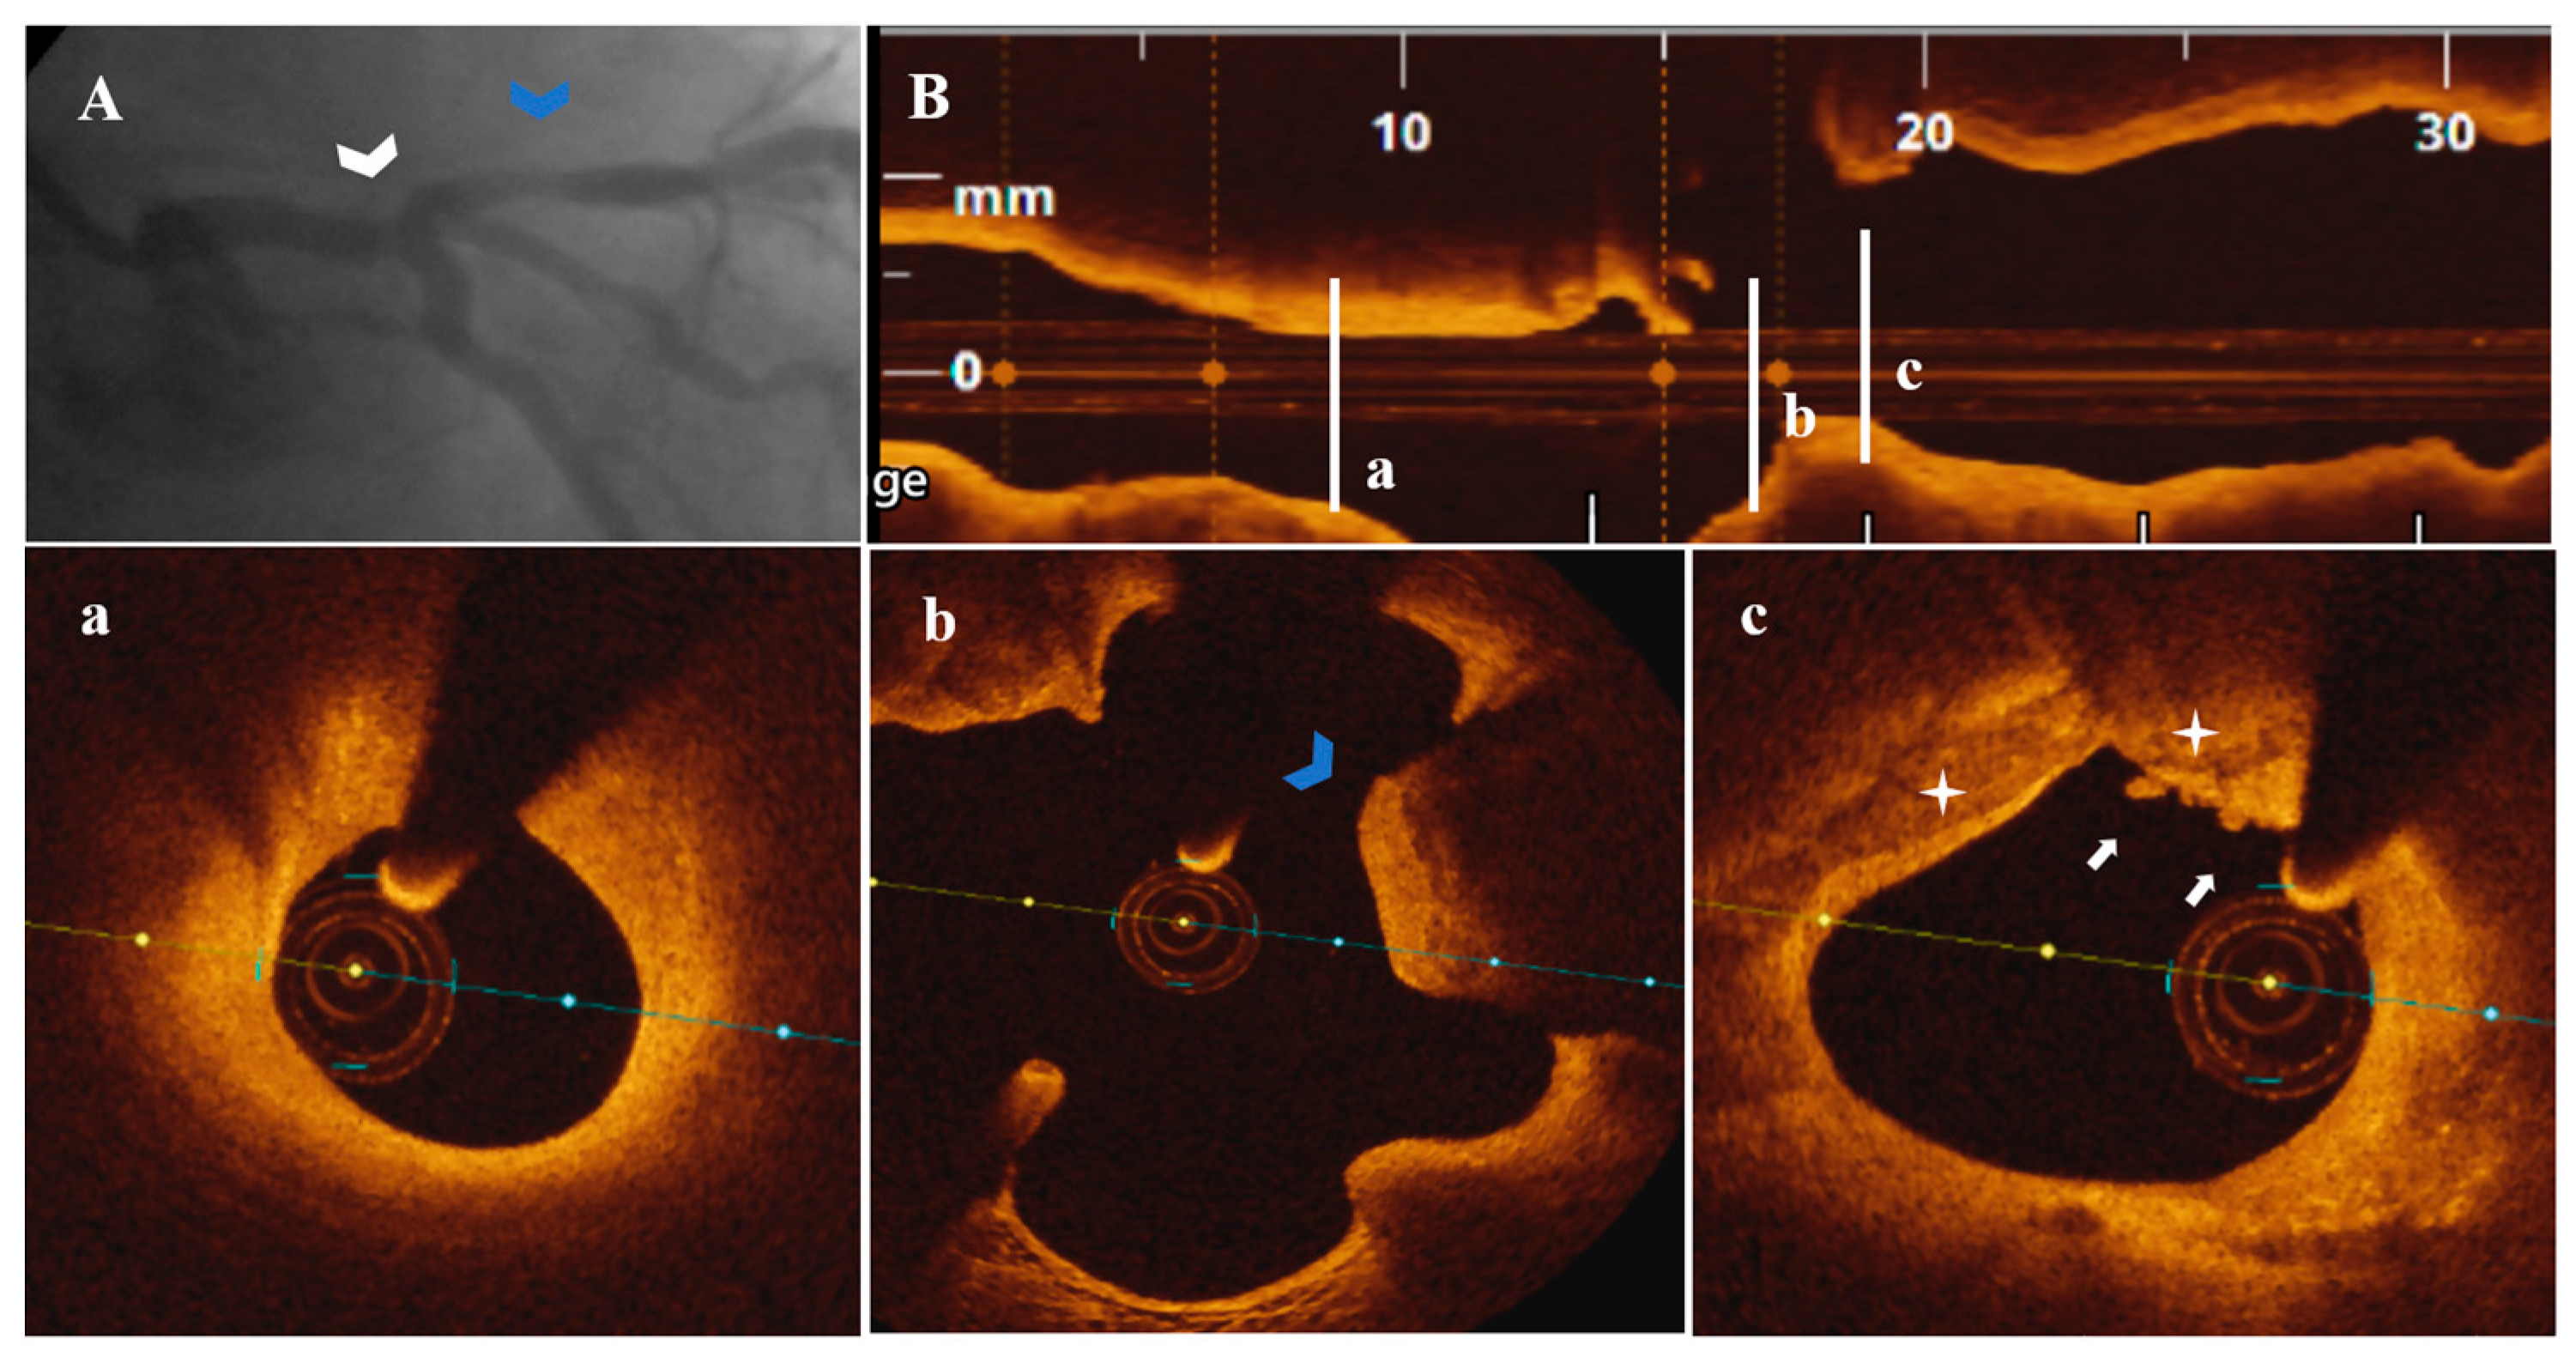

Figure 5.

A 79-year-old patient presenting with UAP. (A) CA—Borderline distal LM (white arrowhead) and nonsignificant proximal LAD (blue arrowhead) stenoses. (B) OCT—LM-LAD plaque longitudinal view. (a) Nonsignificant LAD stenosis without marks of complication. (b) Calcified protrusion (blue arrowhead) following a (c) PE-SCP (white star) with white thrombi (white arrow) at the level of a nonsignificant LM stenosis (area stenosis = 44.9%).

In 2/7 patients, PE-SCP coexisted with other acute marks of plaque disruption. As seen in Figure 4, there was a long LM-LAD plaque presenting PE-SCP with white thrombus (Figure 4c) and HCP (Figure 4d) in the significant and respectively nonsignificant LAD lesions, alongside eruptive CN (Figure 4a) and CP (Figure 4c,e). In the same patient, an eruptive CN with red thrombus determined the significant LM stenosis (Figure 4f). In Figure 5, there is PE-SCP with small thrombi (Figure 5c) followed by a CP (Figure 5b) at the LM level.